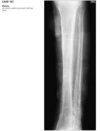

well-defined, eccentric, radio-

lucent lesion with a thin, sclerotic border adjacent

to the cortex of the distal tibia.

Repeat 7 yrs later shows well defined sclerotic lesion in same location.

Humerus radiograph shows identical lesion with pathological fracture

Diagnosis: Fibrous cortical defect or NOF

> 2cm = NOF and <2cm = FCD.

Can be polyostotic - associated with NF, FD, Jaffe-Campanacci syndrome.

Lesions originally

arise adjacent to the physis, and as limb lengthen-

ing occurs, they migrate away from the joint.

typical FCD or NOF is radiolucent; has a thin, scle-

rotic margin; and shows no periosteal reaction.

Rarely, it may be expansile or undergo pathologic

fracture.

Involutes during adolescence and becomes sclerotic.